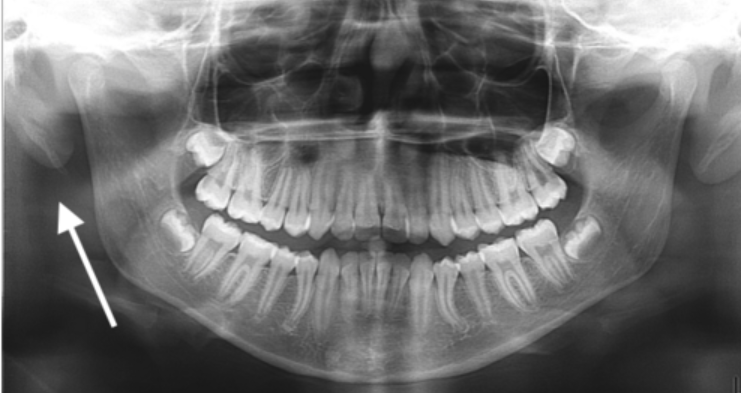

in the circle, indicated by the arrow

styloid process